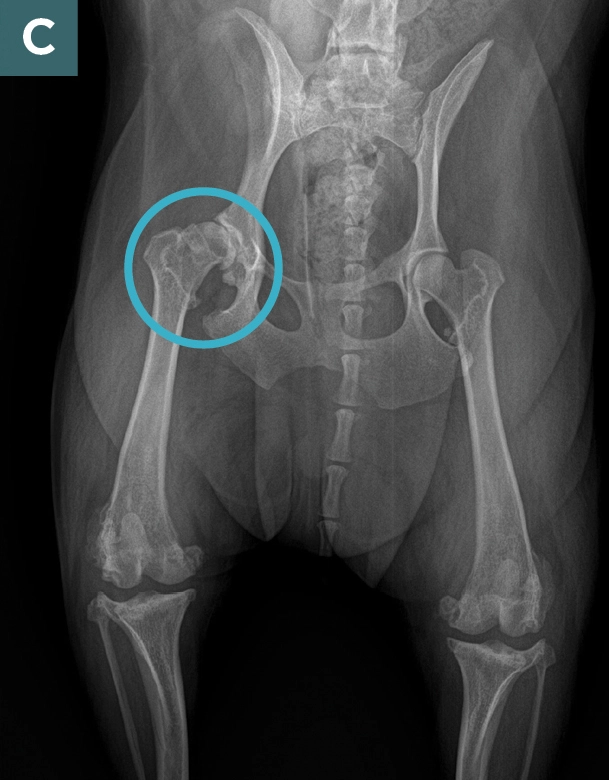

What does arthritis look like on x-ray?

Arthritis on x-ray shown by:

a) joint narrowing (cartilage thins so looks like bone on bone)

b) excess bone growth (osteophytes)

c) bone hardens just below cartilage (subchondral sclerosis)

Interestingly it has been shown for humans and dogs, that just because x-rays show advanced arthritis doesn't mean the dog (or human) will be disabled. Dogs can be severely affected by arthritis but show little arthritis on x-ray, and the reverse is true. A dog can present quite healthy and well but have a lot of joint changes indicating severe arthritis.

We don't get x-rays to confirm a diagnosis but, in fact, to exclude other diseases. For example, the symptoms of hip arthritis can be very similar to bone cancer of the hip, so in this case an x-ray helps to confirm arthritis and rule out cancer.